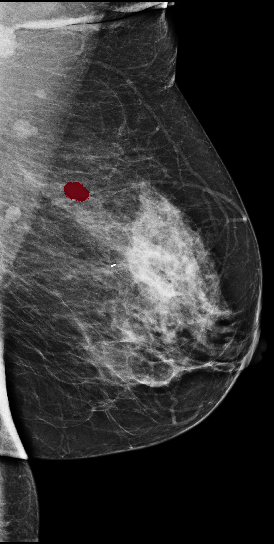

[\capbeside\thisfloatsetupcapbesideposition=left,top,capbesidewidth=6cm]figure[13cm] prior latest highlight prior latest L-CC Refer to caption Refer to caption Refer to caption L-CC Refer to caption Refer to caption L-MLO Refer to caption Refer to caption Refer to caption L-MLO Refer to caption Refer to caption (a) (b)

Figure 3: Test examples where AlignLocalCompare performs better than the single-exam baseline. A breast with a malignant finding shown in (a) (malignant finding is highlighted with red) and one with a benign lesion shown in (b). AlignLocalCompare predicts malignancy with 0.97 probability for (a) and 0.04 for (b), whereas the baseline predicts 0.73 for (a) and 0.24 for (b). There is about a year gap between two exams for both patients.